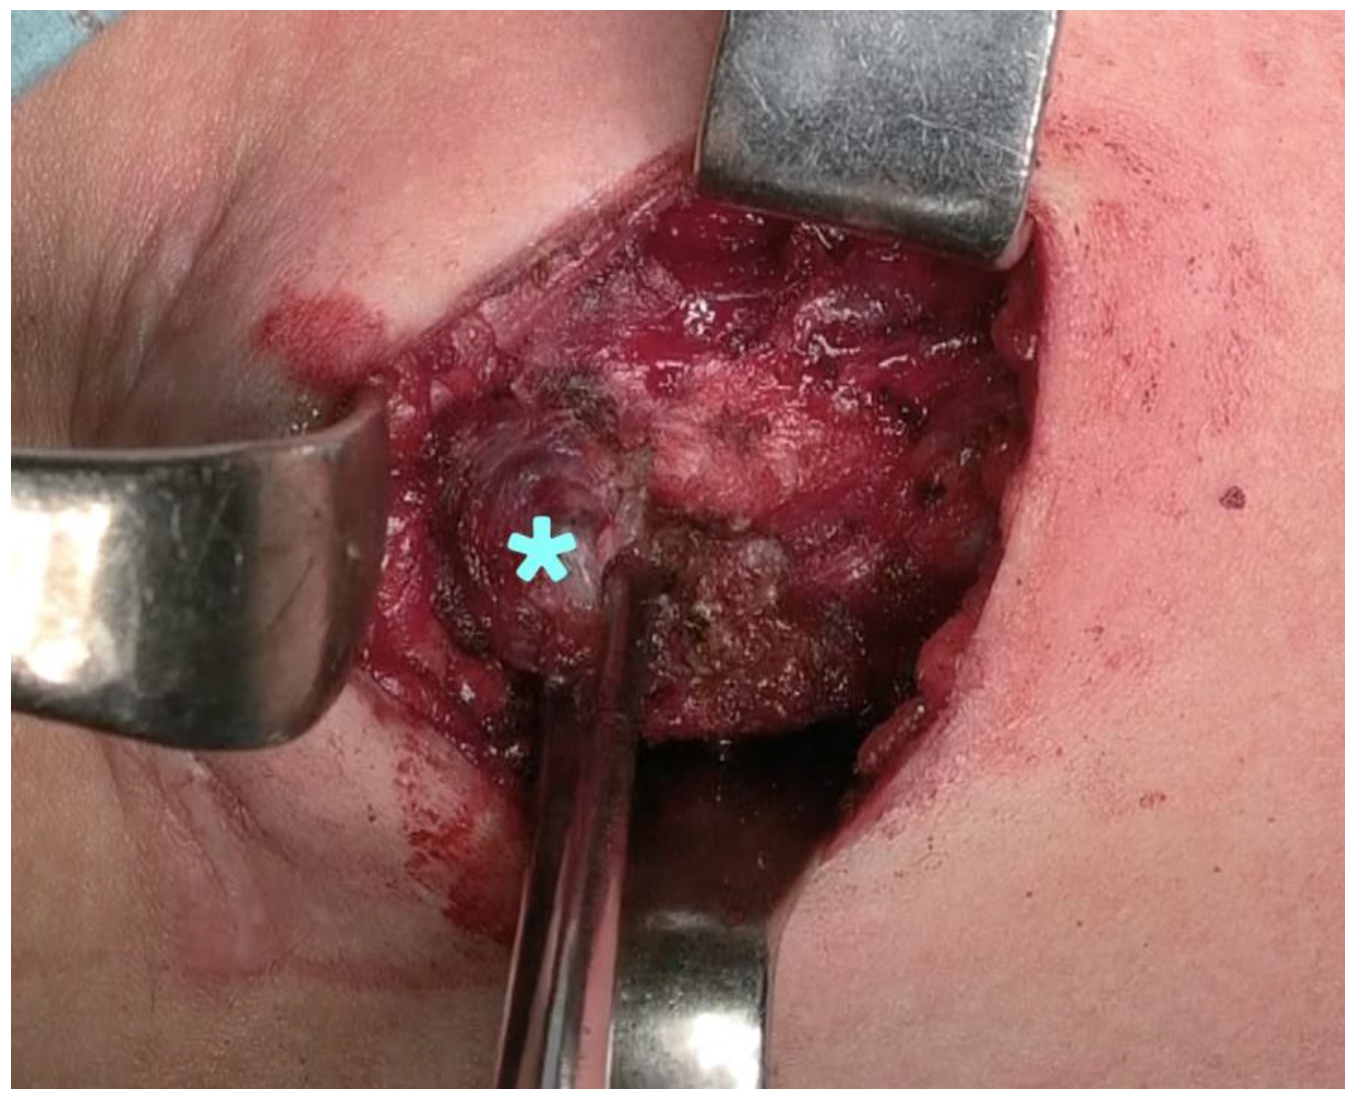

First Application of the Orbeye™ 4K 3D Exoscope in Recurrent Papillary Thyroid Cancer Surgery

2. Case Presentation